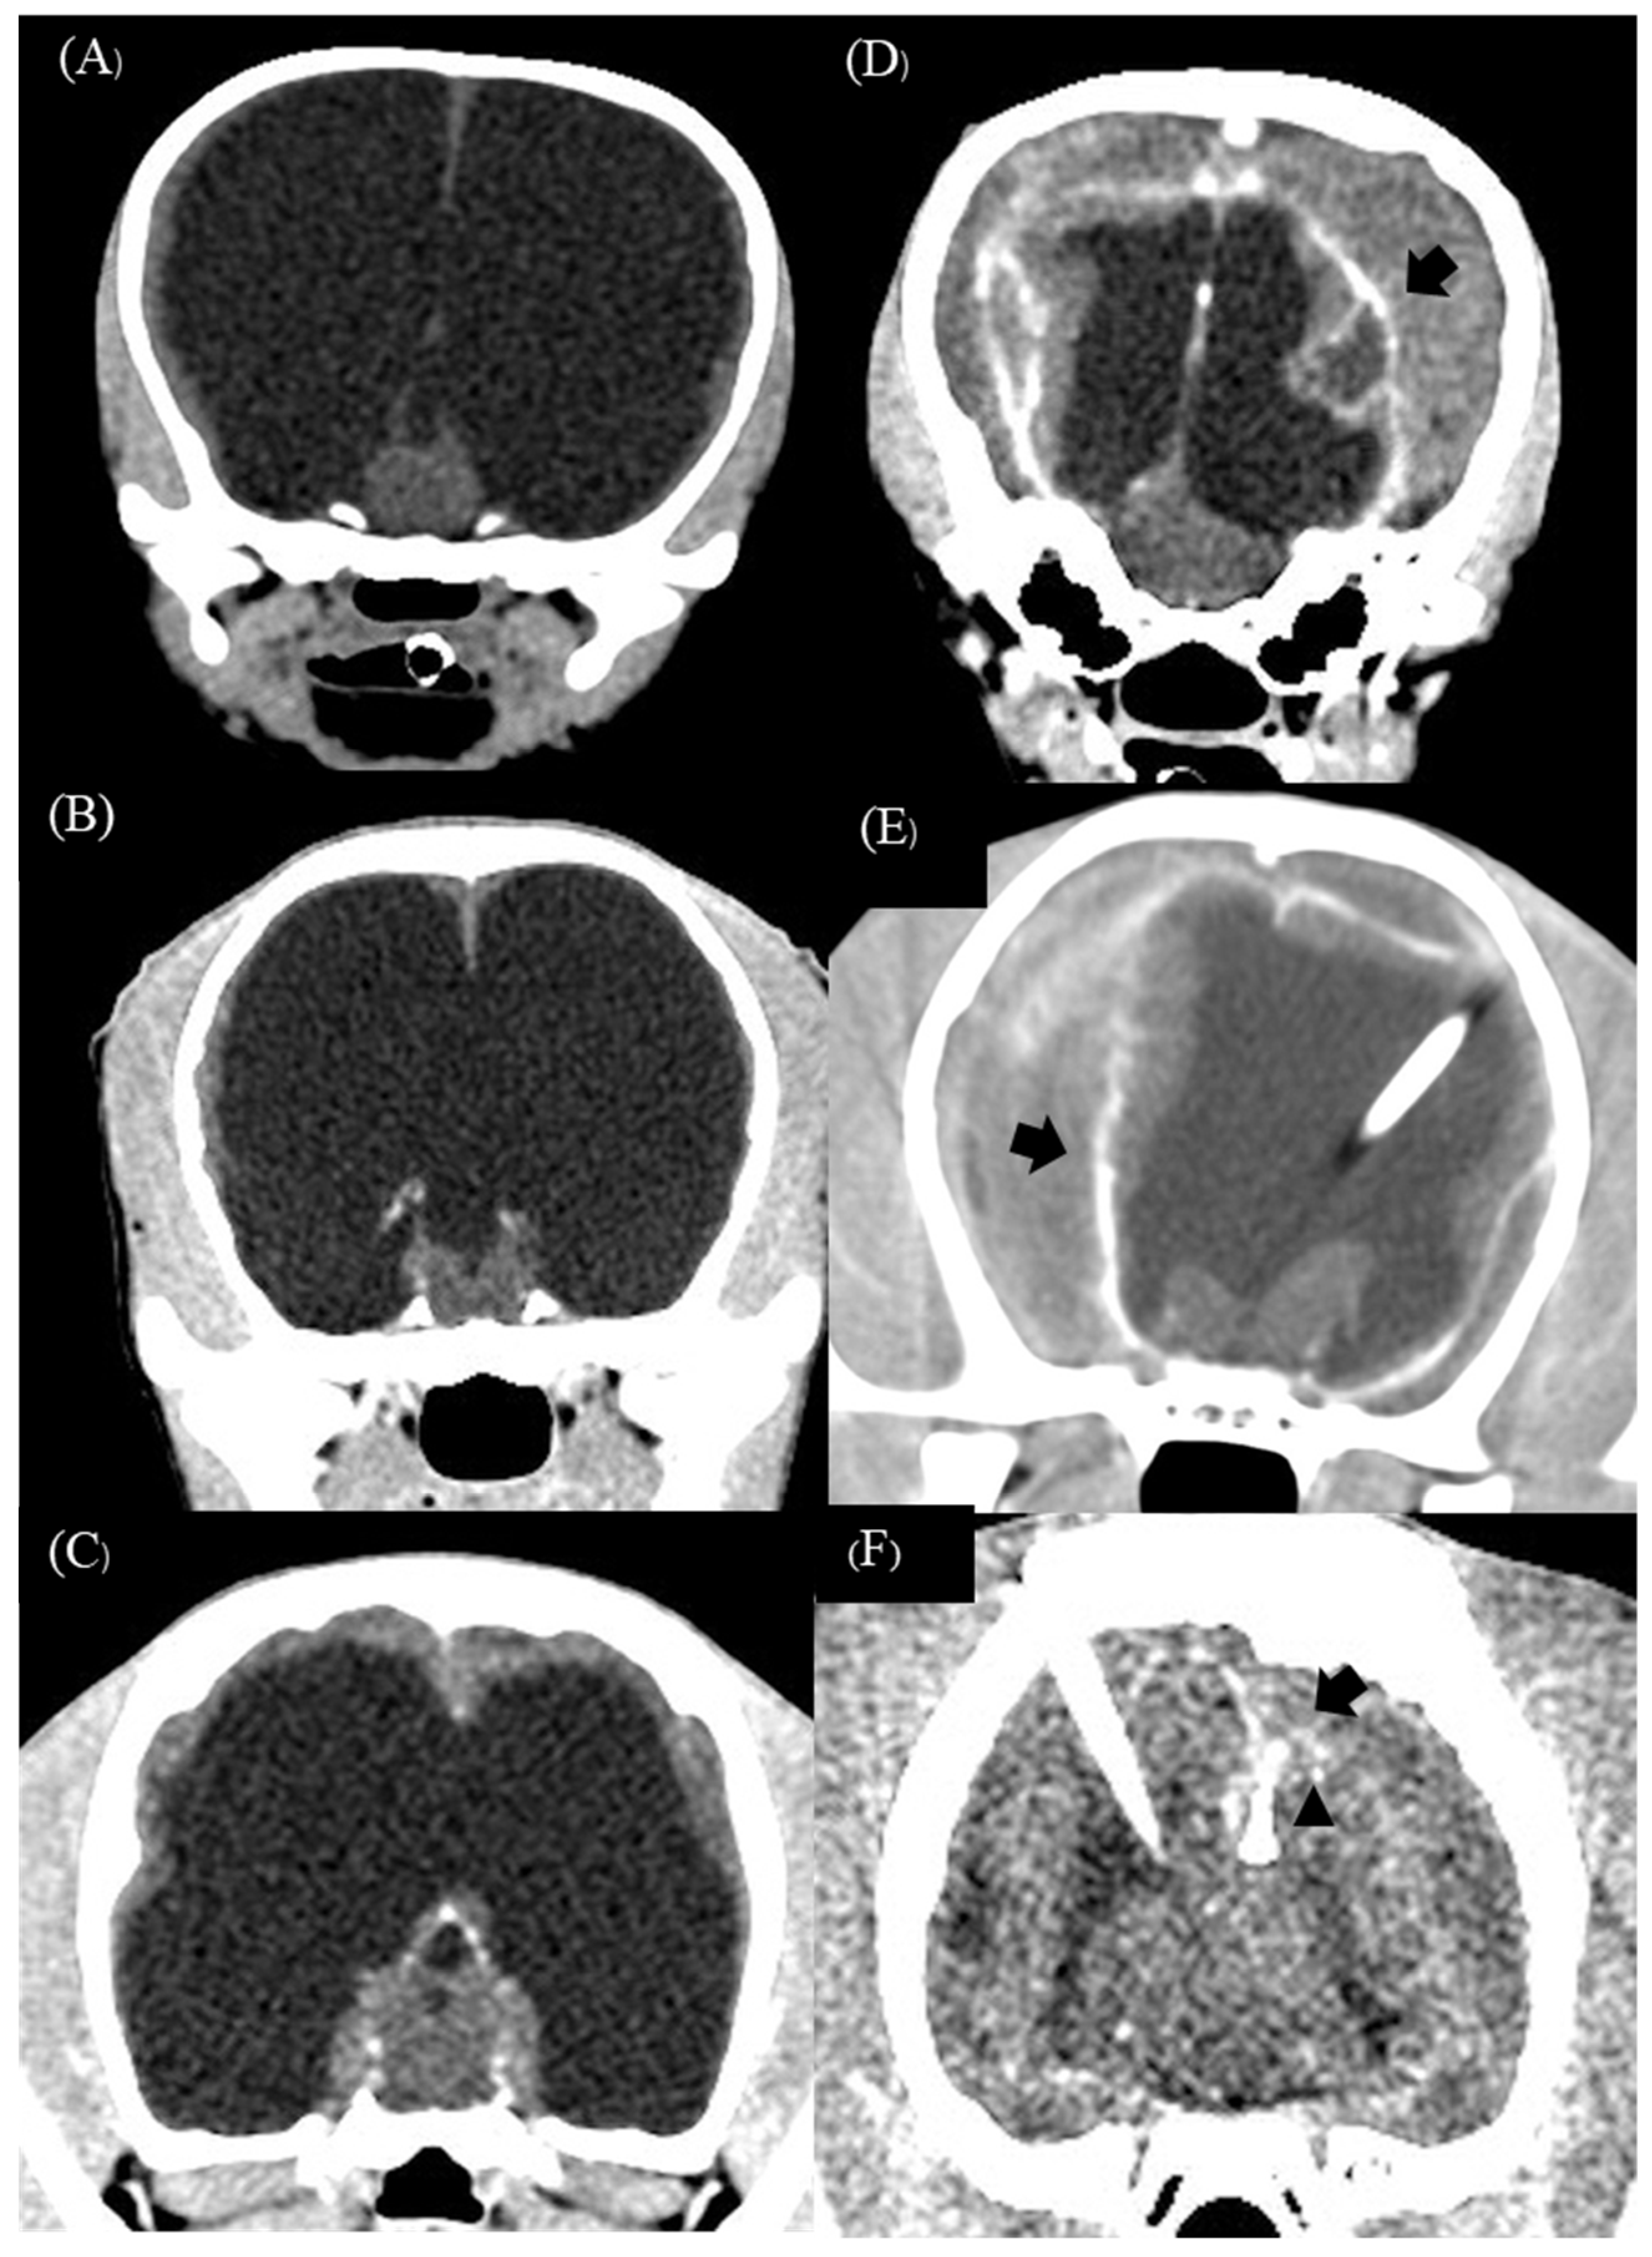

3.1.3. Complication

3.2.3. Complication

| 1 | Crossbreed | male | 2 | 2.4 | 3 | Mesencephalic aqueduct stenosis | 2.94 | 142.10 | 60 | 57.77 | Bilateral subdural hematoma and empyema |

| 2 | American Pitbull | male | 4 | 13.7 | 8 | Obstruction of interventricular foramen | 2.57 | 205.40 | 98.60 | 51.99 | Bilateral subdural hematoma and empyema |

| 3 | American Bully | male | 6 | 9.7 | 4 | Mesencephalic aqueduct stenosis | 3.68 | 139 | 7.57 | 94.55 | Bilateral subdural hematoma and empyema |

| 4 | Jack Russel Terrier | male | 6 | 1.6 | 12 | Mesencephalic aqueduct stenosis | 2.20 | 132 | 57.70 | 56.28 | Bilateral subdural hematoma |